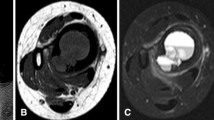

Role of MR imaging in surgical staging

The main role of MR imaging is in the evaluation of whether a tumor is located in the extramedullary or intramedullary compartments. MR imaging is able to detect tumor involvement of the adjacent muscle compartments, neurovascular structures, growth plate, and joints [9, 11, 18, 19]. Evaluation of neurovascular involvement can be accurately assessed on T1-weighted images because of the contrast between the tumor (low signal intensity) and the fat surrounding the neurovascular bundle (high signal intensity) [20]. Other sequences with fat-saturation such as T2-weighted FSE, proton-density weighted, and contrast-enhanced axial T1-weighted sequences have also been used to evaluate neurovascular bundle involvement [13, 21, 22] (Fig. 6). MR imaging features of neurovascular bundle involvement include complete encasement and/or infiltration of the vessels [13]. Involvement of the vascular structures may require vascular reconstruction while involvement of the lumbosacral plexus or sciatic nerve may preclude limb salvage [16].

A 13-year-old girl with osteosarcoma of the right upper tibia. a Axial unenhanced T1-weighted image shows a soft tissue mass displacing the neurovascular bundle (arrow). The fatty rim surrounding the neurovascular bundle is displaced but preserved. b Axial enhanced fat-saturated T1-weighted image confirms the neurovascular bundle to be intact (arrow)